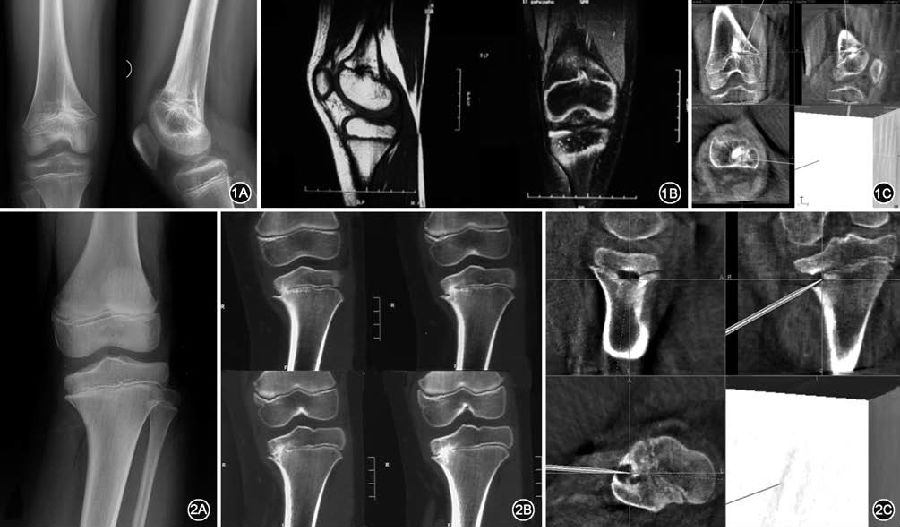

图1 10 岁男性股骨远端骺早闭,术前影像与术中导航相匹配 1A.术前X 线片显示股骨远端偏内侧骺早闭,形成中央型骨桥;1B.术前磁共振示在矢状位和冠状位上骺线中断,骨桥形成;1C.术中导航影像清晰显示出冠状位、矢状位、水平位的骨桥位置,图中所指为磨钻到达位置,引导下进行磨除  图2 11岁男性胫骨近端骺早闭,术前影像及术中骨桥磨除后再次导航确认 2A.受伤3 年后逐渐出现胫骨近端内翻畸形,术前平片未发现明确骨桥;2B.术前CT 检查发现胫骨近端部分层面可见边缘型骨桥;2C.术中磨除骨桥后再次导航,骨桥部位已变成空腔,术中应用指示器于空腔内各点确认骨桥完全磨除